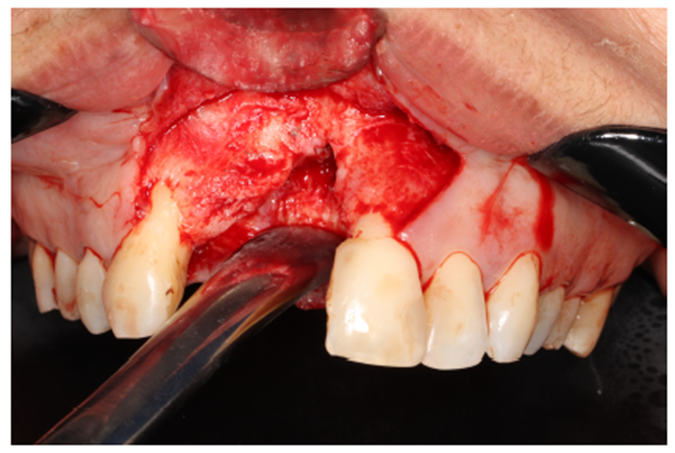

Nos casos de extensa reconstrução óssea, o retalho cirúrgico deve ser realizado à distância para visualização total da área cirúrgica, acomodação do seu futuro material de enxerto, ganho e fechamento total do tecido mole (Figura 4). Outro ponto importante para o sucesso da integração do material de enxerto é a descorticalização do processo alveolar, a fim de levarmos sangue medular com maior quantidade de células osteoprogenitoras. No caso, foi realizado com uma broca tipo lança.